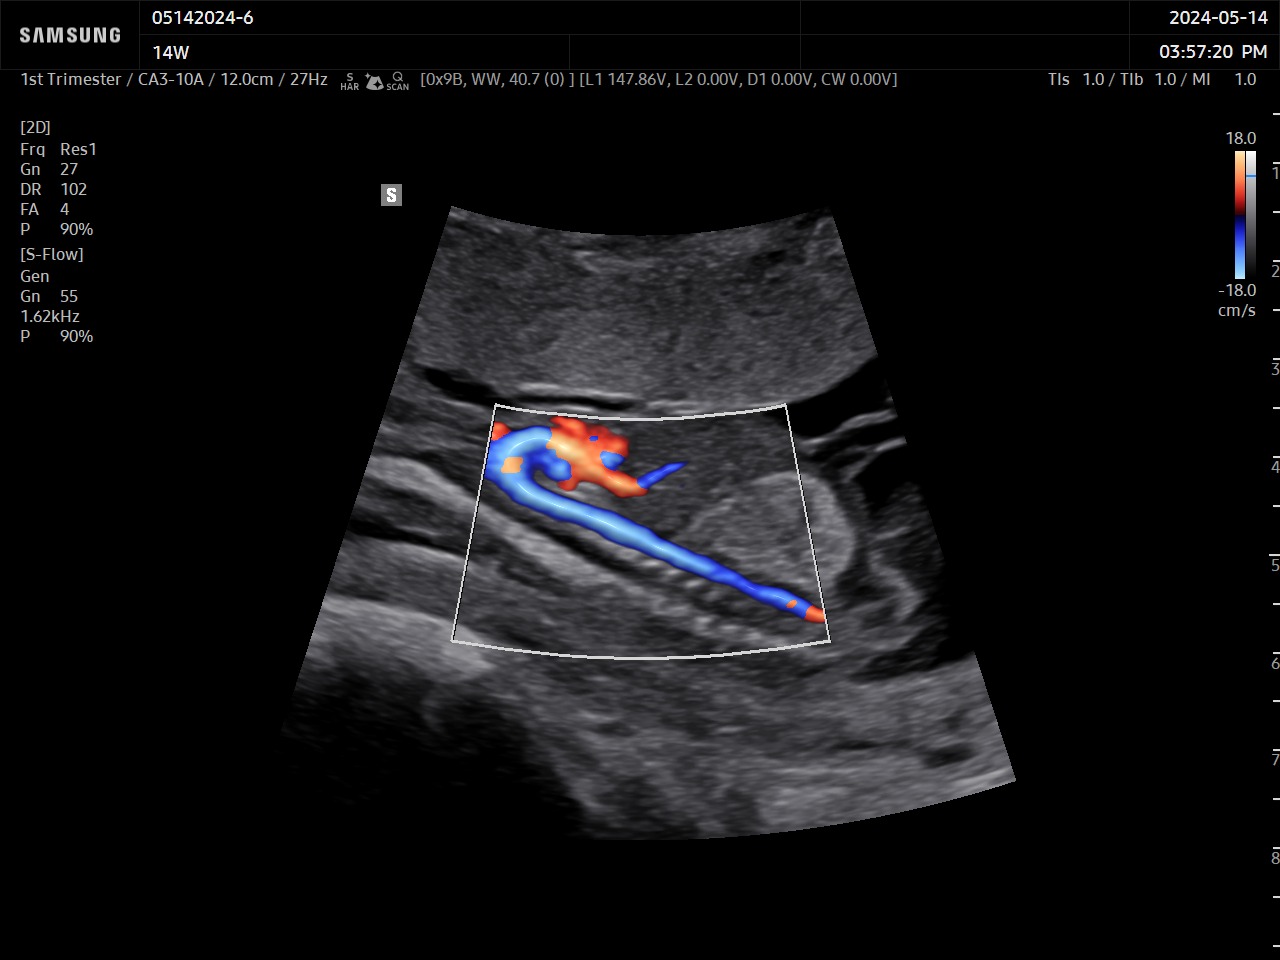

MV-Flow™ offre une nouvelle alternative au Doppler Énergie pour visualiser les flux lents et la microvascularisation des structures. Les hautes cadences images et les filtres d’imagerie avancés permettent au MV-Flow™ de coder le mouvement des hématies en s’abstenant des artefacts de l’imagerie B et ainsi améliorer la résolution spatiale.

LumiFlow™ est un codage de visualisation avec un effet tridimensionnel qui permet d’étudier l’architecture des vaisseaux, de manière intuitive.